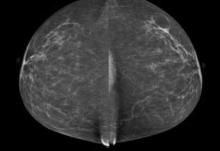

http://glossary.itnonline.com/3d-mammographyHologic Inc. announced that a groundbreaking new study published in Radiology, the Radiological Society of North America scientific journal, found that the addition of three dimensional (3-D) mammography (breast tomosynthesis) screening technology to a 2-D breast screening exam significantly increased cancer detection while reducing the number of false positives.

According to a new market research report "Breast Imaging Technologies Market (Digital Mammography,3D Breast Tomosynthesis, Breast MRI, Breast Ultrasound, Molecular Breast Imaging, Optical Imaging, PET/CT/PEM Modalities) Technology and Market Analysis & Global Forecasts to 2017" is an attempt to showcase the market impact of current and emerging breast imaging technologies having excellent growth potential in the coming five years. The technologies profiled in the report are segmented into Ionizing breast imaging modalities and Non-Ionizing breast imaging technologies on basis of radiation. Ionizing breast imaging modalities include Mammography, 3D Breast Tomosynthesis, Cone beam Computed Tomography (CBCT), Positron Emission Mammography (PEM), Molecular Breast Imaging (MBI), Positron Emission Tomography (PET) and Breast Specific Gamma Imaging (BSGI). The various Non-ionizing modalities for breast screening covered in the report are Breast MRI, Optical Imaging, Breast thermography and Breast Ultrasound.